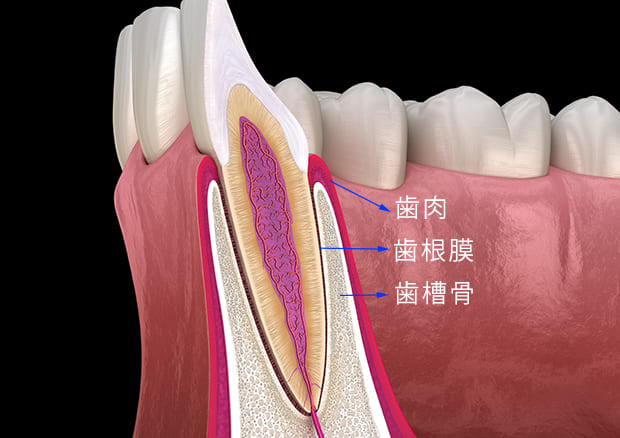

歯周病は、歯を支えている周りの組織(歯肉、歯根膜、歯槽骨)が歯周病菌によって破壊されていく感染症です。治療しないでそのまま放っておくと徐々に噛めなくなり、最後には歯が抜けてしまうとても怖い病気で、日本人の35歳以上の多くの8割の人が歯周病に既にかかっていると言われています。

歯周再生療法

歯周病が進行すると、歯の周りにある歯槽骨を吸収するため、歯槽骨がどんどん少なくなっています。この歯槽骨が吸収すると元には自然に戻りません。

この吸収した歯槽骨の形にそって、歯肉が表面を覆っていますので、歯の表面が以前と比べ多く露出しますので、歯が長くなったように見えてしまったり、歯に隙間が空いてしまったり、場合によっては歯がしみるといった症状がでてくることがあります。

従来の歯周病治療では、歯周病が進行して歯が抜けないように病状が進行しないように止める治療しかできませんでした。

しかし、歯周組織再生療法をおこなえば、歯周病により破壊された組織を再生させ、歯をできるだけ元の健全な状態に戻す可能になりました。

ただし、重度の歯周病にはこの再生療法を使っても組織の再生が困難なこともあります。ですので、歯周病でお悩みの方は歯科医師にしっかり診査診断をしてもらいましょう。